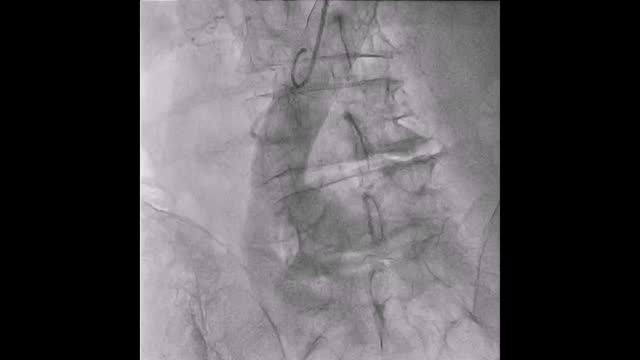

El paciente se traslada a la sala de hemodinamia donde se intenta la extracción del dispositivo. Se utilizan diferentes catéteres lazo de 10, 25 y 30 mm, así como lazos de fabricación con guías largas y cortas intentando movilizar el dispositivo desde diferentes accesos vasculares (acceso bifemoral 6 y 18 Fr y radial 6 Fr) (figuras de la 1 a la 4). Se produce como complicación disección de aorta abdominal con extensión a arteria ilíaca común derecha (figuras 5 y 6) y pérdida total del flujo en extremidad inferior ipsilateral con signos y síntomas de isquemia arterial aguda, por lo que el paciente es trasladado de forma urgente al quirófano de angiología y cirugía vascular. Se realiza disección de aorta abdominal infrarrenal vía laparotomía media con aortotomía longitudinal en el lugar de la localización del cuerpo extraño visualizándose el dispositivo migrado anclado a la íntima-media de la pared arterial. Se procede a su extracción y posteriormente se realiza cierre de aortotomía con parche de pericardio bovino fijando la disección y corrigiendo así el defecto (figuras de la 7 a la 9). El paciente sale de quirófano con pulso pedio bilateral y excelente perfusión distal.